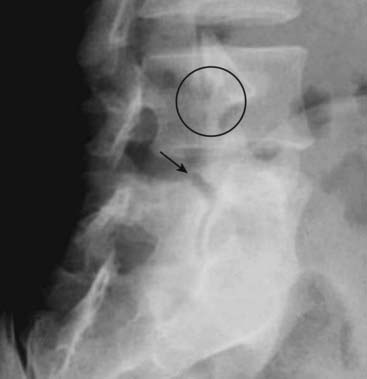

Spondylolysis is easiest to visualize on an oblique conventional radiograph of the lumbar spine or CT in which a lucency representing the break in the “neck” of the Scottie dog (the “collar” on the Scottie dog) may be seen in the pars interarticularis (Fig. 24-12).

Figure 24-12 Spondylolysis.

Spondylolysis is believed to be due to a combination of factors including a congenitally dysplastic pars that is subjected to certain strains that eventually lead to a stress fracture of the pars (solid black arrow). You might recognize the break as a “collar” on the “neck” of the Scottie dog (see Fig. 24-3). A normal pars is shown in the black circle. Spondylolysis allows the affected vertebral body to slip forward on the body below it (spondylolisthesis).